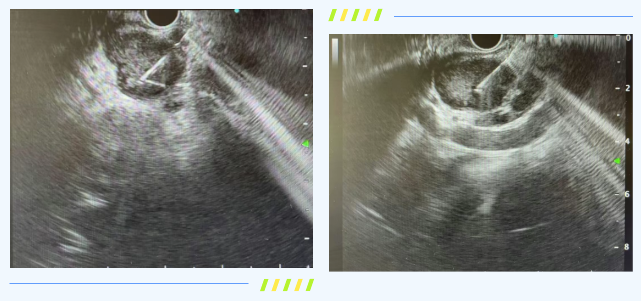

胃镜超声引导下细针穿刺术,是在普通胃镜前端加装超声探头,如同为内镜医生配备了“透视眼”。

手术在超声下实施定位引导,经胃镜活检孔道伸入专用穿刺针,精准穿刺至病变部位,抽取少量组织或细胞送检。这项技术能够避开血管及重要脏器,在微创条件下判断病变的性质、分型、分期为诊断提供“金标准”,为后续治疗方案的制定奠定基础。